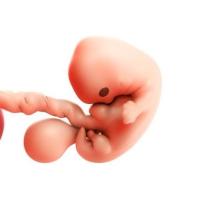

4° settimana: l’embrione assume una forma a “C”, il cuore va a localizzarsi centralmente, si formano i primi abbozzi del viso, del tratto respiratorio e dell’apparato digerente;

5° settimana: la parte della testa inizia a crescere di dimensioni e si formano gli abbozzi degli arti e compare l’attività cardiaca;

6° settimana: la testa cresce e si flette sul torace. Iniziano a svilupparsi orecchie, occhi e naso, il cuore si suddivide in 4 camere e si delineano le dita.

7° settimana: il volto inizia ad assumete un aspetto più definito. Il canale intestinale cresce molto più velocemente della parete addominale ed ernia al di fuori di essa, si formano reni, fegato e pancreas;

8° settimana: si forma il cuoio capelluto, i padiglioni auricolari e le palpebre. Sono riconoscibili le dita di mani e piedi;